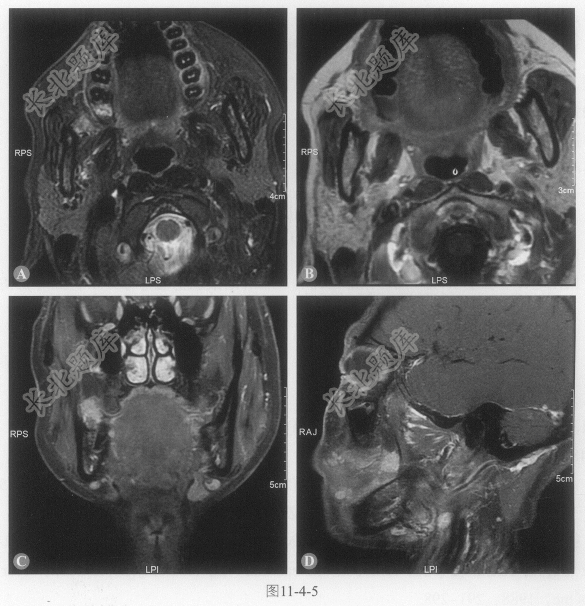

患者女性,47岁,右颊肿物8个月。8个月前活检病理:右颊上皮性肿瘤,鳞状上皮异形增生。复查MRI,表现如图11-4-5。

- 多项选择题1.病变描述正确的是:

A、病变累及右侧颊黏膜,形态不规则

B、深部累及颊间隙

C、同侧颊肌浸润

D、翼内肌前缘不清,可能累及

E、下颌骨升支前缘未累及

- 多项选择题2.再次活检证实,考虑黏液表皮样癌,上述影像特征中,提示病变恶性可能的征象是:

A、病变形态不规则,边界欠清

B、病变浸润同侧颊肌

C、病变累及颊间隙

D、病变累及翼颌间隙

E、病变累及咬肌间隙